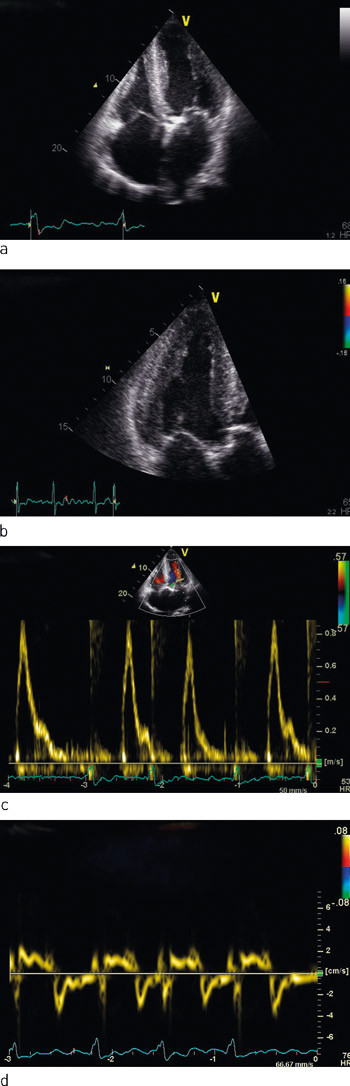

Ekkokardiografi viste moderat dilatert venstre ventrikkel med lett til moderat fortykket vegg. Endediastolisk indre diameter var 6,6 cm, septumtykkelse 1,4 cm og bakre veggs tykkelse 1,2 cm (fig 1). Venstre ventrikkels ejeksjonsfraksjon ad modum Simpson biplan var ca. 30 %. Det var tegn til forhøyet venstresidig fyllingstrykk. Aortaklaffen var trikuspid med betydelig forkalkning av alle tre kusper, redusert åpningsbevegelse og betydelig aortastenose, med areal 0,9 cm2 beregnet etter kontinuitetslikningen. Det var en liten, sentral aortainsuffisiens. Mitralklaffen hadde slanke segl og en liten insuffisiens. Det forelå biatrial forstørrelse (venstre atrium 29,5 cm², høyre atrium 20,5 cm²). Blodstrømshastigheter i mitralostiet, vevshastigheter i mitralringen og dilatert venstre atrium indikerte samlet at det forelå restriktiv fylling av venstre ventrikkel. Myokard hadde et påfallende, granulært ekkokardiografisk uttrykk, og det ble mistenkt primær myokardsykdom i tillegg til klaffefeil. Koronarangiografi viste kalk i proksimale koronarkar, men ingen signifikante stenoser.

Transvenøs biopsi av endomyokard viste avleiring av amyloid (fig 2), der immunohistokjemisk fremstilling avdekket nedslag av transtyretin (prealbumin) (fig 3).